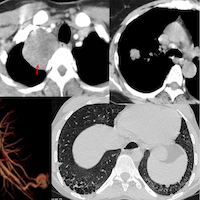

COD 117 - A Progressive Mixed Pattern Preceding the CTD Diagnosis

51-yrs old in 2012 presented with a fibrotic NSIP pattern.

The video describes the temporal evolution from 2017 to 2025 with a mixed pattern of fibrotic NSIP, fibrotic OP and DPO/CiOP and a final CTD diagnosis that was established only early this year with evidence of PPF.